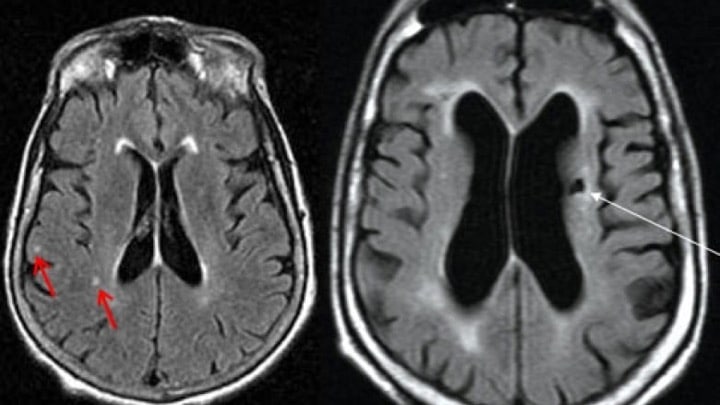

سکته خاموش با انواع دیگر سکته از جمله سکته مغزی، سکته مغزی ایسکمیک و سکته مغزی خونریزی دهنده متفاوت است.چگونه میتوان سابقه سکته خاموش را تشخیص داد؟اگر سی تی اسکن مغزی یا MRI داشته باشید، تصویر لکههای سفید یا ضایعاتی که نشانگر سلولهای مغزی از کار افتاده است، قابل مشاهده میباشد. به این ترتیب دکتر مغز و اعصاب متوجه سکته خاموش خواهد شد.علائم دیگر به قدری ظریف هستند که اغلب با علائم پیری اشتباه می شوند، مانند:مشکلات تعادلسقوط مکررنشت ادرارتغییر در خلق و خویکاهش توانایی تفکر

اگر سی تی اسکن مغزی یا MRI داشته باشید، تصویر لکههای سفید یا ضایعاتی که نشانگر سلولهای مغزی از کار افتاده است، قابل مشاهده میباشد. به این ترتیب پزشک متوجه سکته خاموش خواهد شدآیا آسیب ناشی از این سکته قابل جبران است؟هیچ راهی برای جبران آسیب دائمی ناشی از کمبود اکسیژن رسانی به سلولهای مغزی وجود ندارد. پس سکته خاموش تا پایان عمر عوارض خود را دارد.با این حال، در برخی موارد قسمتهای سالم مغز ممکن است عملکردهای پیشین مناطق آسیب دیده را انجام دهند. در نهایت، اگر سکتههای خاموش ادامه پیدا کند، توانایی مغز برای جبران کاهش مییابد.آیا میتوانید مسائل شناختی را درمان کنید؟براساس موسسه ملی اختلالات عصبی و سکته مغزی، درمان توان بخشی میتواند به افرادی که به دلیل سکته مغزی برخی از تواناییهای خود را از دست دادهاند، کمک کند. برای دریافت کمک میتوانید به این متخصصین مراجعه کنید:درمانگران فیزیکیآسیب شناس گفتارجامعه شناسانروانشناسانبرخی از پزشکان داروهای آلزایمر را برای افراد مبتلا به زوال عقل عروقی تجویز میکنند، اما هنوز تاثیر این داروها برای این بیماران اثبات نشده است.